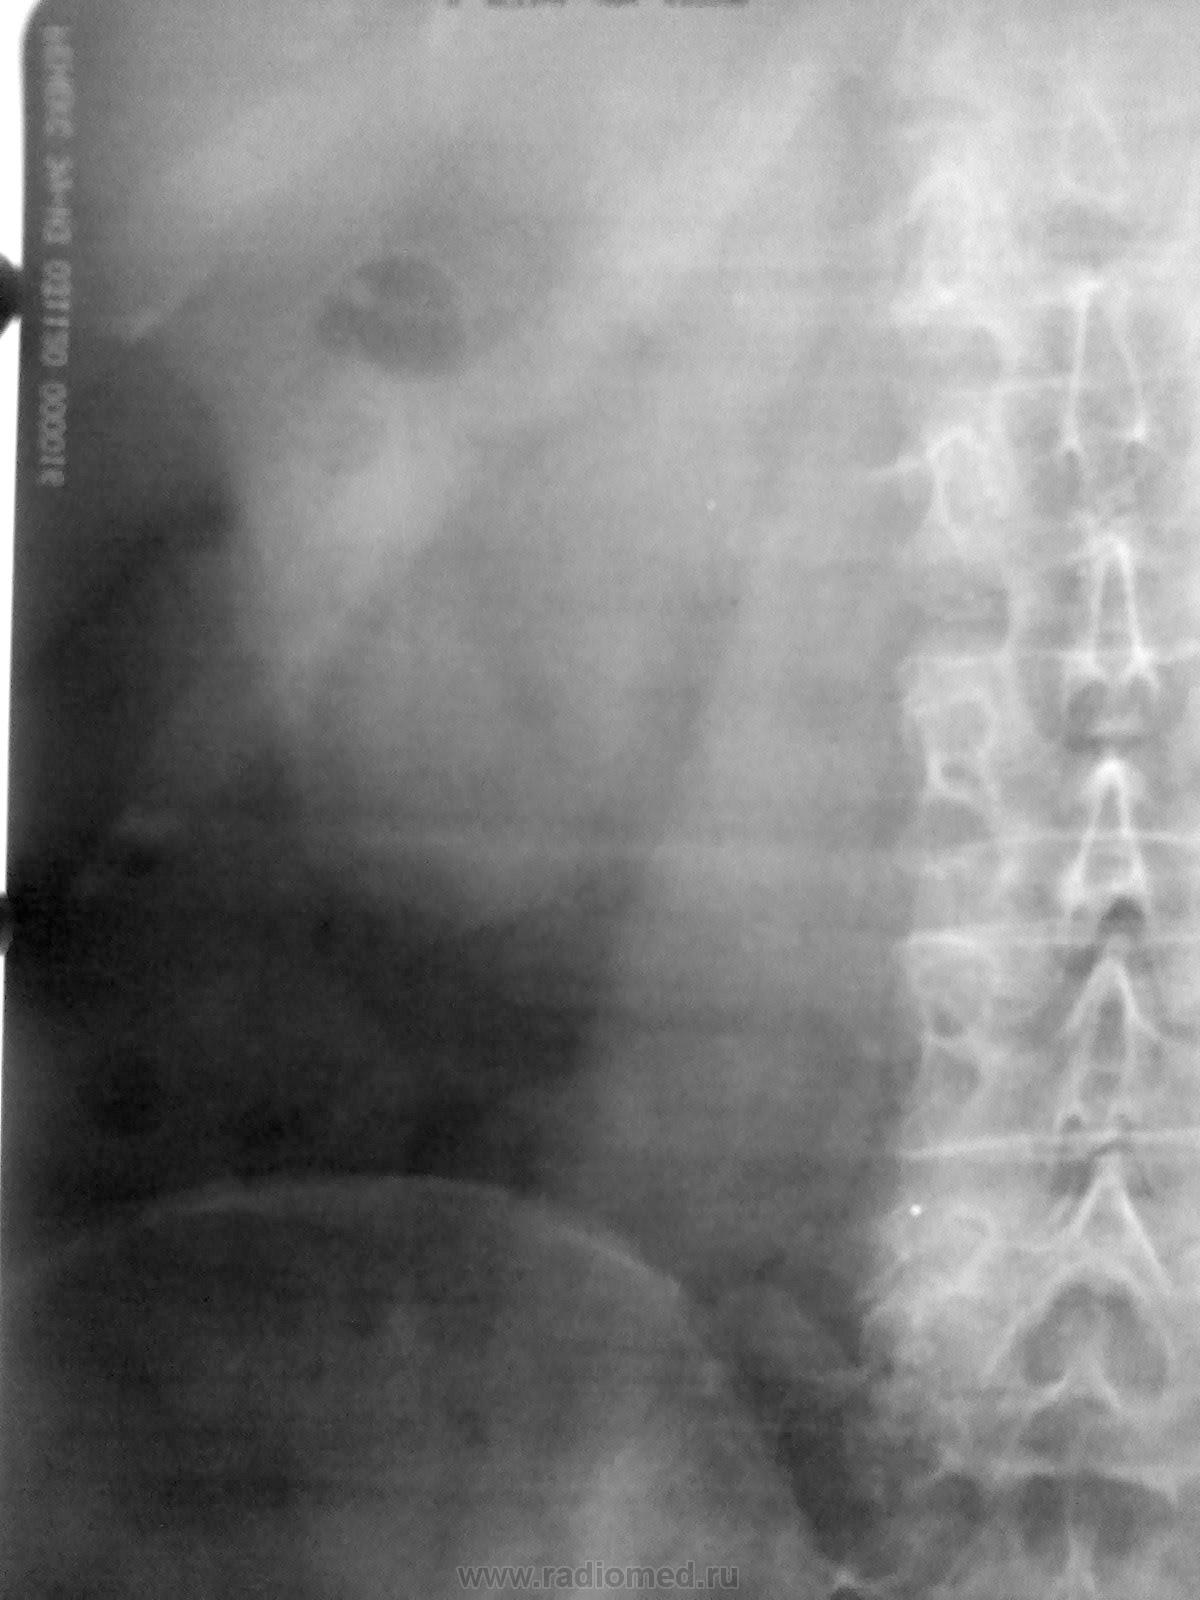

Киста правой почки с признаками атипии

Пациентка 48 лет, обследована на УЗИ - выявлена полостное образование в правой почке, направлена на урографию.

Можно конечно предположить дополнительное образование правой почки по верхне-наружному контуру...но действительно, где же в\в урография?

В верхнем сегменте правой почки что-то...  что значит по узи полостное образование? Жидкостное? Если жидкостное, то оно не может так выглядеть. Может, что-то жиросодержащее? Например, ангиомиолипома, дермоид. Бывают ангиомиолипомы с большим преобладанием жира, но, к сожалению, не знаю как они выглядят на рентгеновском снимке. Больше не приходит ничего в голову, что могло давать такую картину.

На экскреторке аналогичная картина, потому газ в кишке отпадает, контрастирования ЧЛС не было. Проследить за дальнейшим развитием ситуации не удалось, это я подрабатывал в ведомственной больнице, знаю лишь, что пациентку в дальнейшем отправили в г.Красноярск в ЖД больницу. В протоколе УЗИ не указывалось содержимое полости.